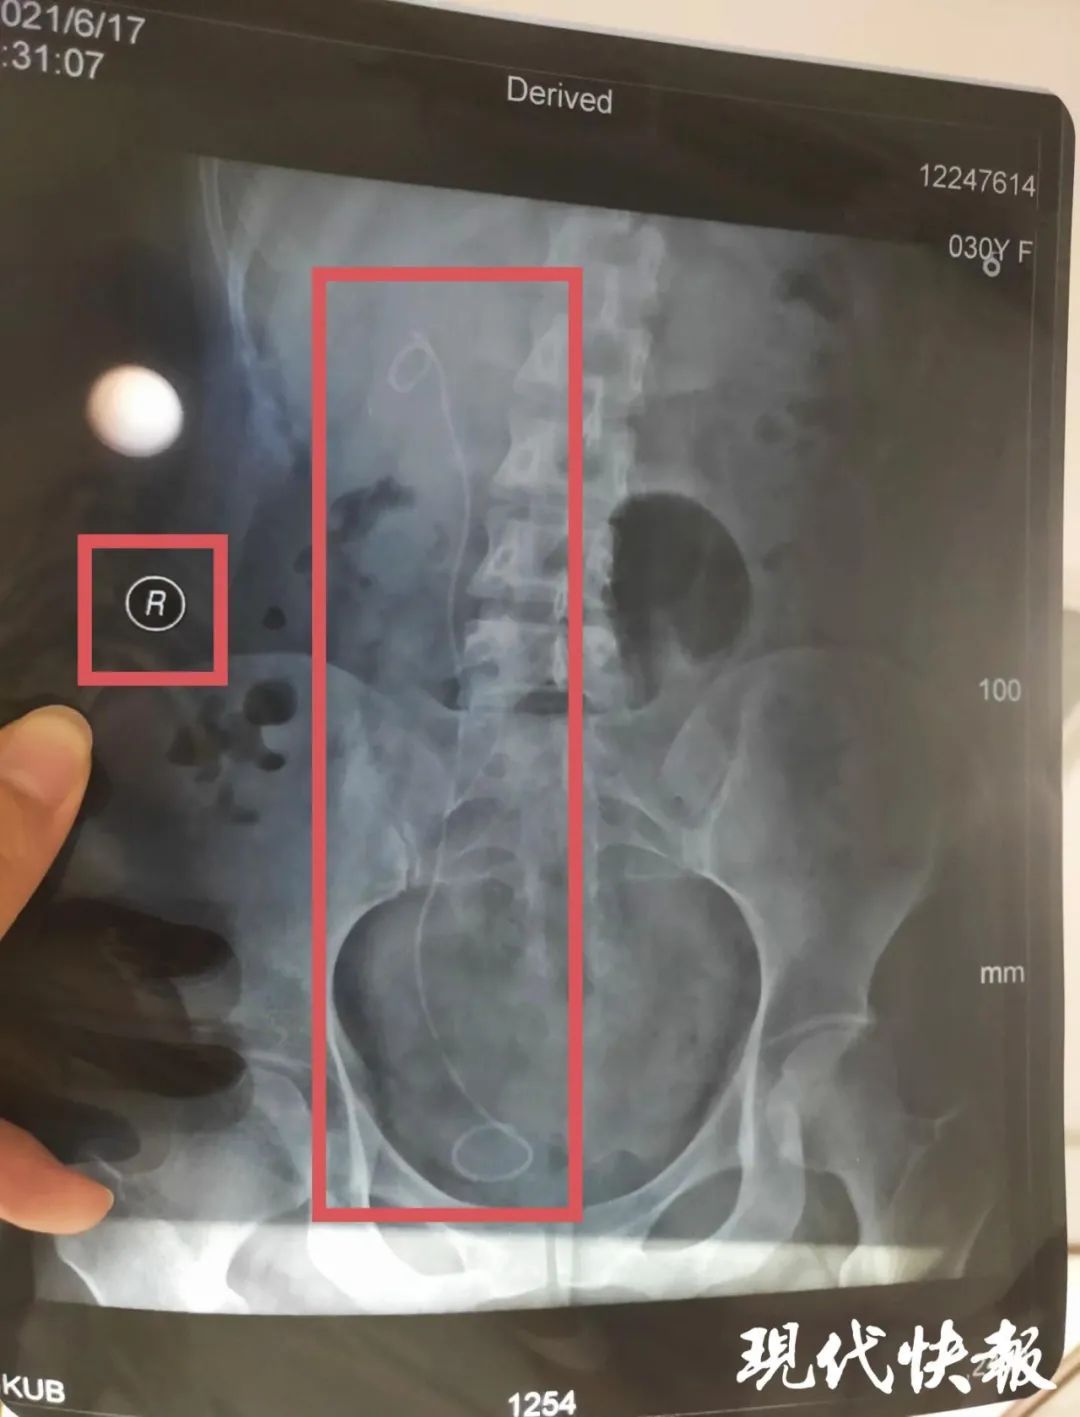

盐城市民朱女士因左侧输尿管狭窄伴左肾积水,前往复旦大学附属华山医院诊治,办好一系列手续后,2021年4月19日住院,4月21日签订手术知情同意书。手术知情同意书显示,拟对左侧输尿管镜检备扩张/内切开。直到出院一个多月后复查时,她才意外发现,手术期间,医生竟然“把左右给搞错了”,在右侧输尿管无异常的情况下,医生在右侧输尿管内安装了支架管。

最终,这起医疗事故经上海市静安区卫生健康委员会移交上海市医学会组织鉴定,认定朱女士遭遇构成四级医疗事故,医方承担完全责任。当初,参与这起手术的医生共三人,包括主刀医生姜某某、一助胡某以及二助邹某某。令朱女士没想到的是,2022年7月,上海市静安区卫生健康委员会对这起医疗事故中一助胡某作出“警告”的行政处罚。理由是作为这起医疗事故的责任医师,胡某违反了卫生行政规章制度或者技术操作规范,造成严重后果。